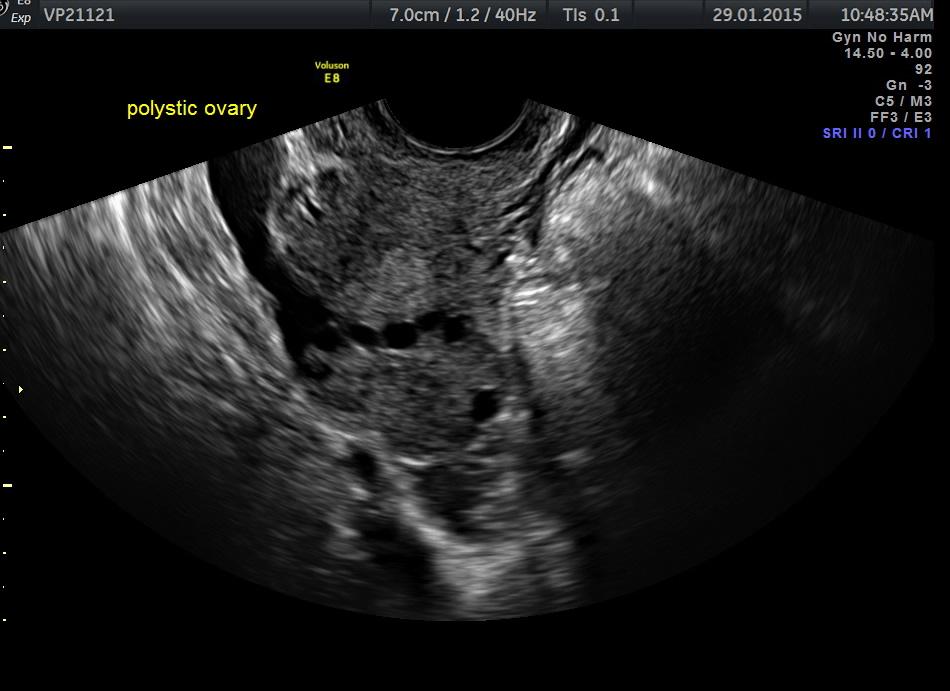

Conditions like PCOS prevent regular egg release.

- Ultrasound scans